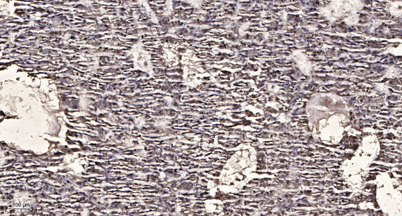

Product name: GRK 5 rabbit pAb

Dilutions: Western Blot: 1/500 - 1/2000. Immunohistochemistry: 1/100 - 1/300. ELISA: 1/10000. Not yet tested in other applications.

Immunogen: The antiserum was produced against synthesized peptide derived from human GRK5. AA range:351-400

Observed Band: 68kD

Background: This gene encodes a member of the guanine nucleotide-binding protein (G protein)-coupled receptor kinase subfamily of the Ser/Thr protein kinase family. The protein phosphorylates the activated forms of G protein-coupled receptors thus initiating their deactivation. It has also been shown to play a role in regulating the motility of polymorphonuclear leukocytes (PMNs). [provided by RefSeq, Jul 2008],